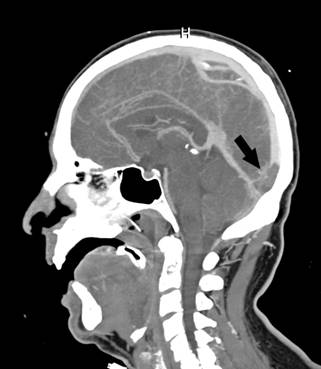

Paciente de 52 años de edad con antecedente de hipertrigliceridemia familiar que ingresa a nuestra institución por cuadro de neumonía bilateral por COVID-19. Al sexto día de internación (y día 16 desde la fecha de inicio de síntomas) evoluciona con cefalea y náuseas y 24 horas después presenta crisis tónico clónica generalizada y deterioro posterior del sensorio con requerimiento de intubación orotraqueal, por lo cual se inicia tratamiento con levetiracetam. Requiere asistencia respiratoria mecánica durante 7 días. Se realiza angioTC de vasos intracraneales que evidencia trombosis a nivel de la prensa de Herófilo, seno transverso, vena anastomótica de Labbé y vena yugular derecha. Se inicia anticoagulación con enoxaparina en dosis de 1 mg/kg cada 12 horas. En exámenes de laboratorio presenta los siguientes valores: ferritina 2933 ng/mL (valor normal 4.6 -204 ng/mL), eritrosedimentación 1ª hora 67 mm (valor normal menor a 20 mm), proteína C reactiva (PCR) cuantitativa 5.9 mg/dL (valor normal menor a 0.8 mg/dL), LDH 451 U/L (valor normal 125 -220 U/L), anticuerpos anticardiolipina IgM 15 MPL e IgG 1 GPL (valor normal menor a 10), anticuerpos anti β2-glicoproteína IgG e IgM 1 U/mL (valor normal menor a 5), factor V Leiden negativo y homocisteinemia 8 µmol/L (valor normal 5 - 15 µmol/L), recuento plaquetario en valores normales durante toda la internación y nivel de actividad anti-Xa posterior al inicio del tratamiento con HBPM de 1,28 U/mL. Intercurre con fibrilación auricular de alta respuesta ventricular que requiere tratamiento con amiodarona. Posterior a la extubación comienza a referir trastornos visuales transitorios, y en su examen neurológico se evidencia dismetría en prueba índice-nariz derecha. En dicho contexto se realiza RMN de cerebro que evidencia lesiones isquémicas en hemisferio cerebeloso derecho y región occipital izquierda en relación al territorio vascular venoso comprometido. Evoluciona favorablemente con estabilidad desde el punto de vista clínico y neurológico, y egresa con tratamiento con acenocumarol.

Figura 2. AngioTC venosa corte sagital que muestra ausencia de contraste a nivel de la confluencia de los senos, compatible con presencia de trombo (flecha negra)